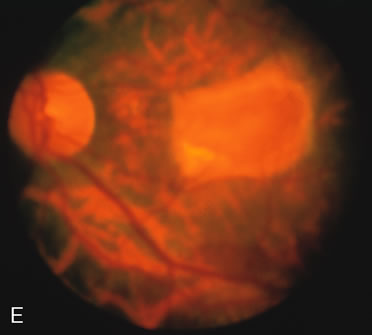

FA plays an important role in the understanding of this rare disorder. In the earliest manifestations of the disease, FA shows a single, isolated choroidal neovascular membrane unassociated with other causes of a membrane, such as drusen or angioid streaks (Fig. 13).25 Presumably this membrane is the cause of the subsequent hemorrhagic maculopathy with secondary disciform scarring, occurring initially in the macula but often extending throughout the retina.

Fig. 13. Hereditary hemorrhagic macular dystrophy (pseudoinflammatory macular dystrophy of Sorsby). Fluorescein angiography in this family member demonstrates that the earliest finding is an isolated choroidal neovascular membrane B). Despite laser photocoagulation, a hemorrhagic maculopathy developed in this eye (C, D) and eventually a disciform scar (E) formed, as it had in the fellow eye, and in the eyes of other affected family members.

Abnormal choroidal perfusion, manifested on FA as a delay in choriocapillaris filling, has been seen in the restudy of some of Sorsby's initial pedigrees.26 This unusual pattern has been related to the histopathologic finding of a “confluent, lipid-containing, amorphous deposit found between the basement membrane of the RPE and the inner collagenous layer of Bruch's membrane.”27